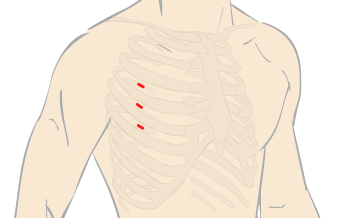

1cmほどのキーホール(鍵穴)を3カ所開け、ロボットアーム(鉗子)や内視鏡カメラを挿入して手術を行います。3D内視鏡カメラにより、術野を鮮明な3D映像で患部を拡大視野で捉えることができ、ロボットの鉗子をミリ単位の操作してオペを遂行します。

“ダビンチ”キーホール手術は、手術支援ロボット“ダビンチ(da Vinci Surgical System)”を用いたロボット手術です。開胸することなく、骨を切らず、数カ所のキーホールからすべての操作が遂行できるので、術中の出血が少なく、術後の痛みも軽く、また大きな傷が残らないため美容的にも優れています。従来のように人工心肺などを使用して遂行していた手術が“ダビンチ(da Vinci Surgical System)”の出現により劇的に変化し、術後経過や術中の体への負担が軽減できるようになりました。“ダビンチ(da Vinci Surgical System)”のような内視鏡手術の進歩は心臓だけでなく、すべての領域で目覚ましい発展を遂げています。現在では珍しいものでは無く標準の手術方法として認められる傾向にあり、新たなアプローチとして広い分野で採用されています。

手術支援ロボット“ダビンチ”を使用したロボット手術は、骨を切らずに小さな傷口のみでオペを行い、出血量・痛みの減少を実現します。早期の社会復帰が可能な手術です。

骨を切ることなく数カ所の

キーホールからすべての操作を

da Vinci Surgical System

手術支援ロボットのダビンチによる手術や小切開手術が可能な場合がございます。ダビンチの手術は小さな3つの穴から手術を行うため従来の方法より痛みや傷の感染、出血量が軽減。